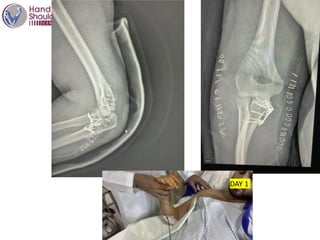

M, 36 yo

Fell from truck

Fracture dislocation R elbow

Neuro vascular ok

What do you do ?

This patient

First reduction on sedation –

DAY 1